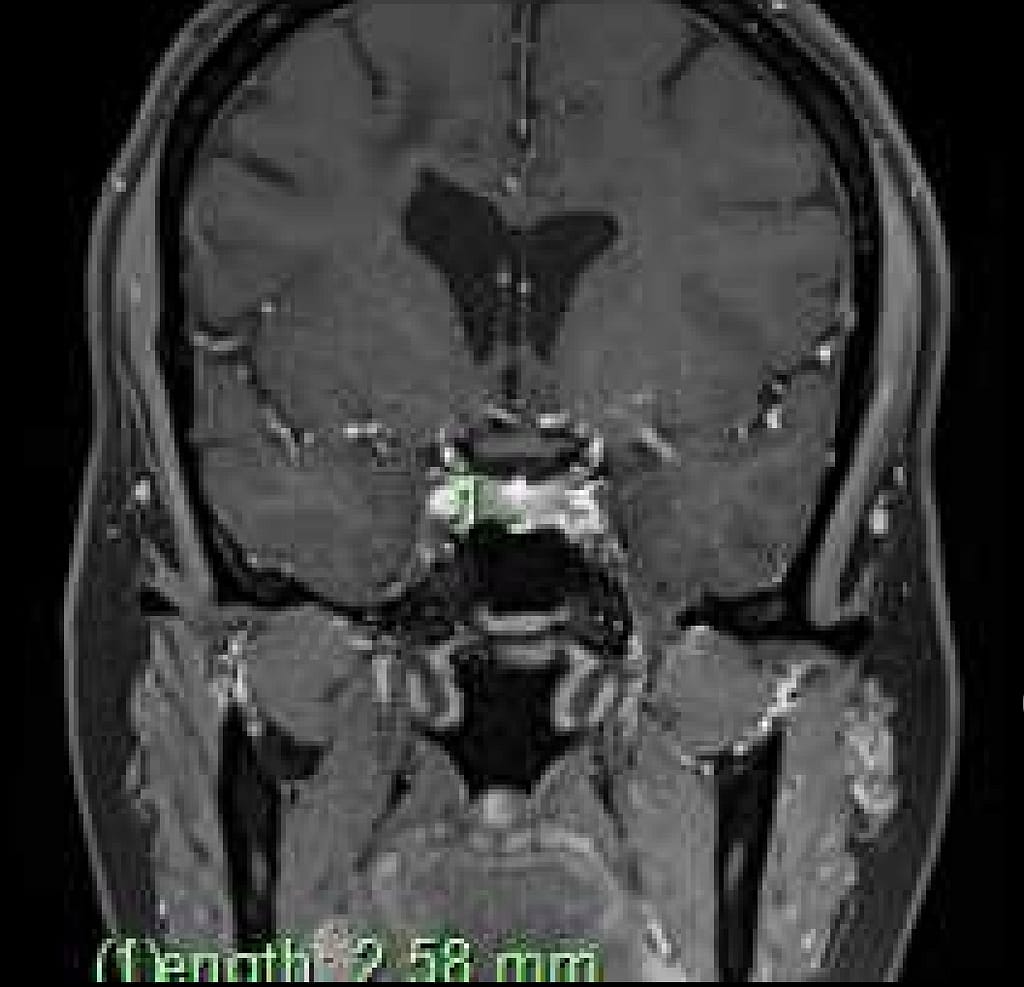

Pituitary tumor imaging

2.58mm in length